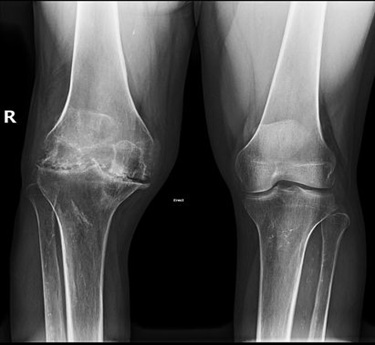

Haemophilic arthropathy

Haemophilic Arthropathy is a joint condition that results from repeated bleeding into the joints, commonly seen in individuals with haemophilia. Over time, this bleeding damages the cartilage and joint lining, leading to pain, stiffness, and reduced mobility. The most commonly affected joints include the knees, elbows, and ankles. The condition typically begins in childhood for those with moderate to severe haemophilia and progresses without proper treatment. Unlike inflammatory arthritis, haemophilic arthropathy is caused by mechanical damage due to bleeding episodes. Early treatment and preventive care can help reduce joint damage and preserve function.

• X-rays may show joint space narrowing, bone erosion, or joint deformity.

• MRI is used to assess joint damage severity and cartilage degeneration.